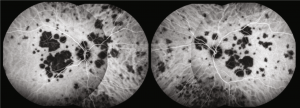

- Fundus autofluorescence (FAF): Placoid lesions generally appear hypoautofluorescent and may have edges that are hyperoautofluorescent. Hypoautofluorescence may persist at borders after lesion resolution.[6]

Fundus autofluorescence: hypoautofluroescent lesions with edges that are hyperautofluorescence(Copyright © 2020 Mariana A. Oliveira et al. Reproduced without modifications from an open access article, Management of Acute Posterior Multifocal Placoid Pigment Epitheliopathy (APMPPE): Insights from Multimodal Imaging with OCTA, distributed under the Creative Commons Attribution License)